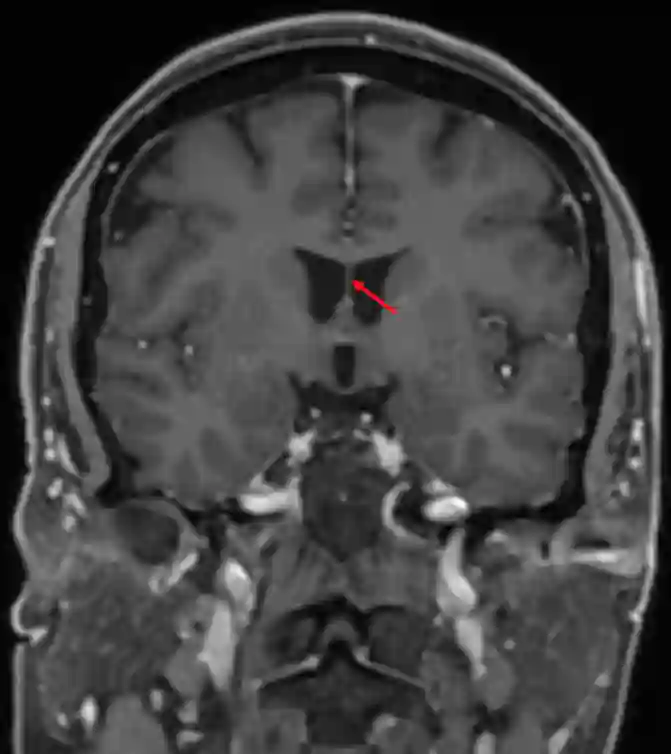

Septum pellucidum im axialen MRI (T1 Sequenz mit Kontrastmittel).Das Septum pellucidum im coronarem MRI Schnitt (T1 Sequenz mit Kontrastmittel).

Das Septum pellucidum im coronarem MRI Schnitt (T1 Sequenz mit Kontrastmittel).